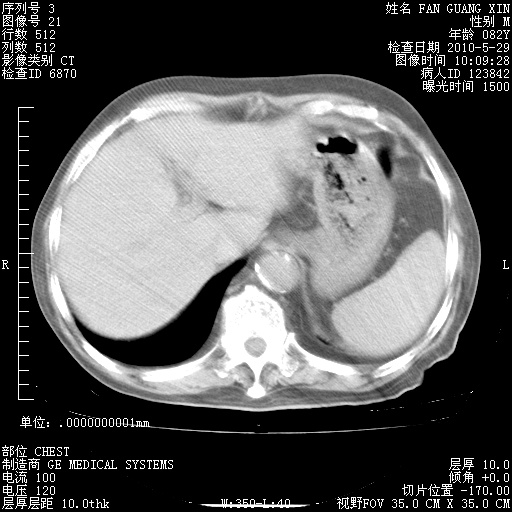

再治疗10天后的肺部CT

阅读此次胸部CT,肺间质渗出性改变较入院时有吸收。目前从体温、白细胞、中性分叶明显增高,肯定存在细菌感染(发生医院感染哦,若无消化道及泌尿系统等感染的依据,肺部感染可能大)。若你院头孢哌酮舒巴坦钠耐药率较高,同意你的方案,若48小时体温仍高,可考虑使用碳青霉稀类抗菌药物,同时可予超声雾化、注意滴数时加大液体量。白蛋白33.30g/L较低哦,需加强营养等支持治疗。